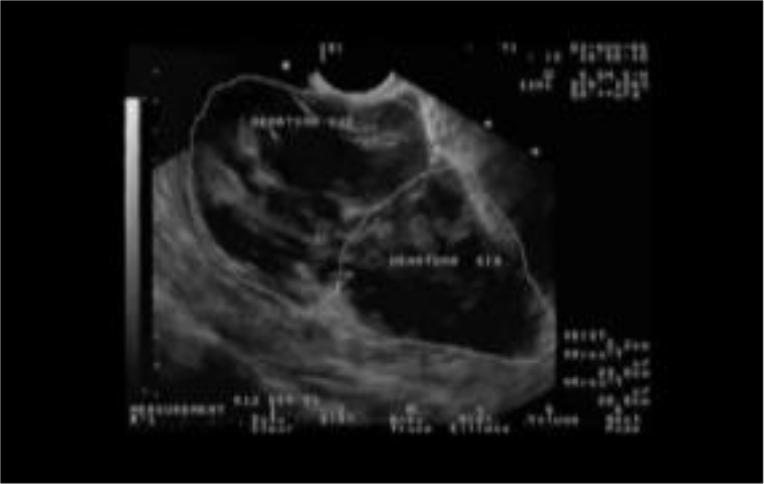

Забрюшинная гематома малого таза (УЗД)

Из архива Е.Ю.Глухова, Екатеринбург